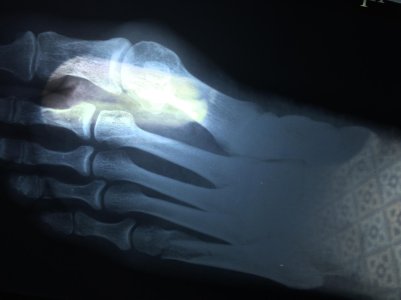

Здравствуйте Василий Иванович! Мне 50 лет, учитель физкультуры, веду активный, здоровый образ жизни. 30 апреля неудачно шагнула, подвернула ногу перелом пятой плюсны. Поставили диагноз: закрытый оскольчатый косой перелом дистальной (дальше слово не понятно) 5 плюсневой кости правой стопы со смещением осколка, замедленная консолидация. Наложили лангету, как "галошу" до голеностопного сустава, через две недели сняли, сделали контрольный снимок. Произошло небольшое смещение, сказали ничего страшного наступай на пятку. Обратилась в другую клинику через четыре дня, снова снимок, доктор сказал:" Рано сняли гипс", наложили сапожок, до середины икры. Скажите пожалуйста, каков прогноз по поводу смещения, нужна ли операция? Как повлияет на ходьбу, смогу ли заниматься физическими нагрузками. Сколько надо еще находиться в гипсе? Заранее благодарна за ответ, спасибо! Ирина.

P.S Сначало перелом был без смешения. Смешение произошло в течении двух недель, после перелома. и Еще скажите пожалуйста, можно ли сейчас приступать на пятку?

Посмотреть вложение 12151Посмотреть вложение 12152Посмотреть вложение 12153 IMG_1208.jpgIMG_1207.jpg